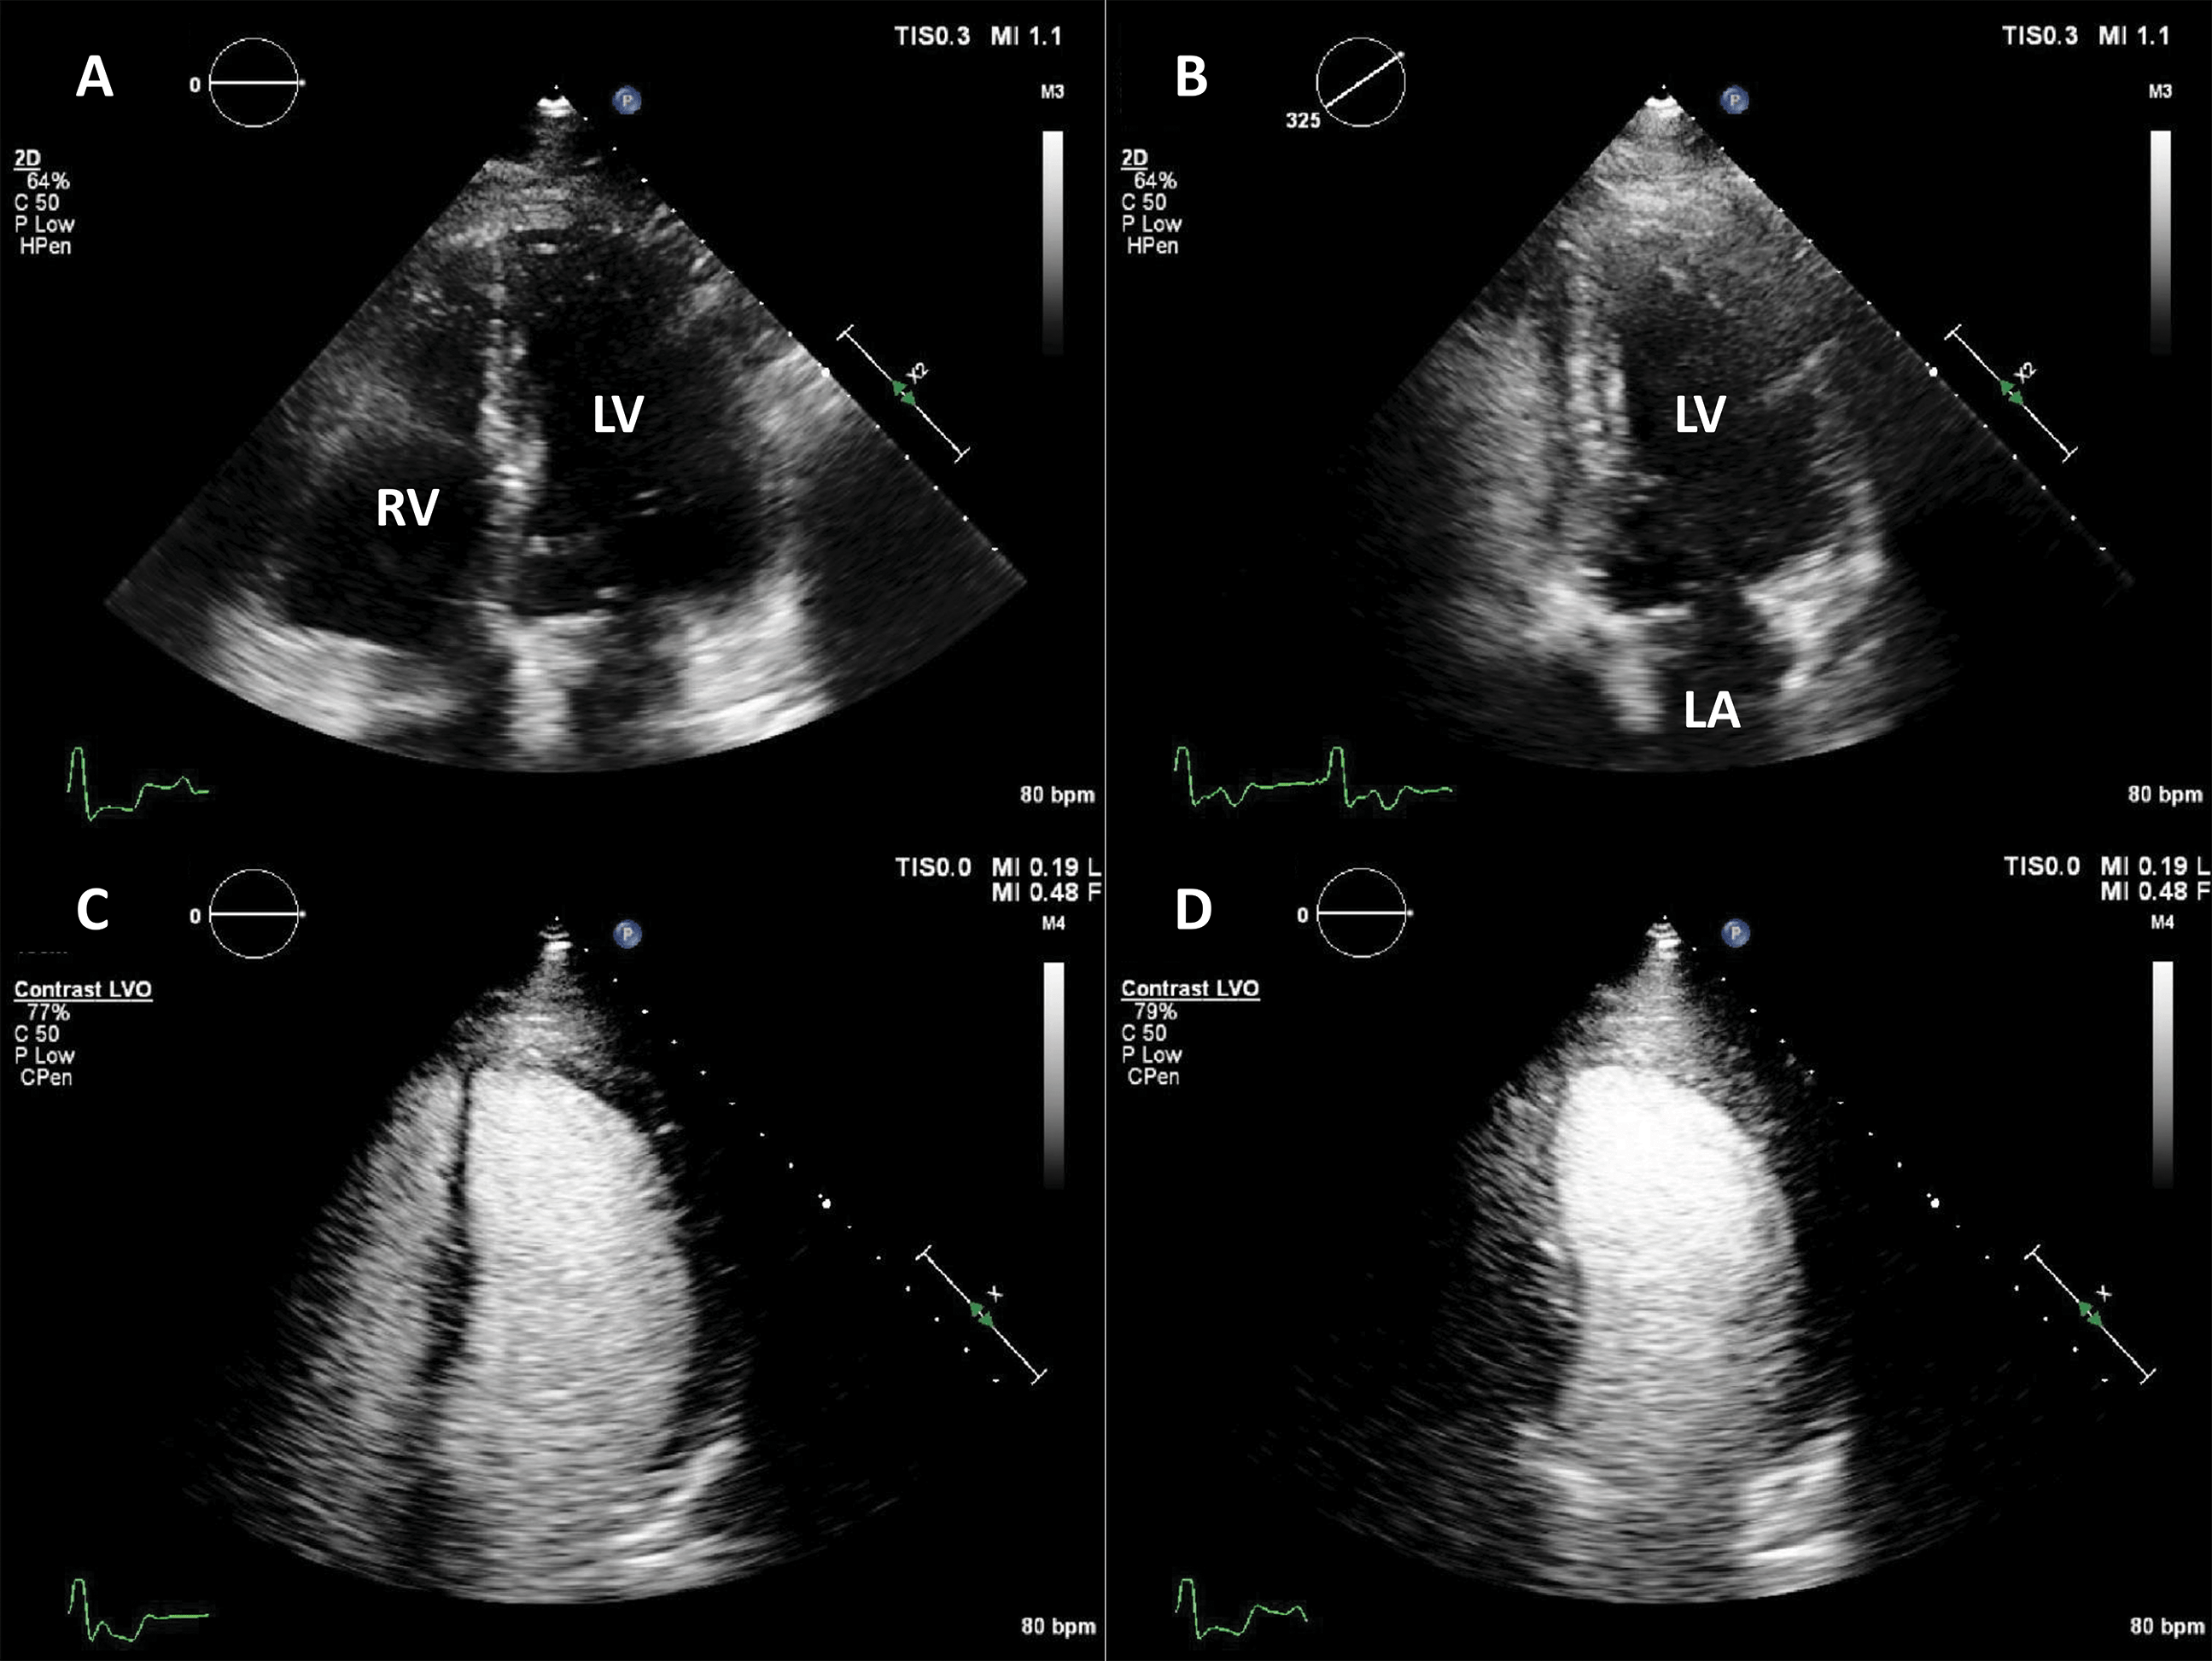

Contrast Echocardiogram/Stress Echocardiogram

Ultrasound contrast agent is used for patients with suboptimal echocardiogram images. This helps physicians to accurately interptret the images. The contrast agent used is NOT a dye (i.e non-iodinated) and does NOT affect the kidneys. You are able to drive after the test.